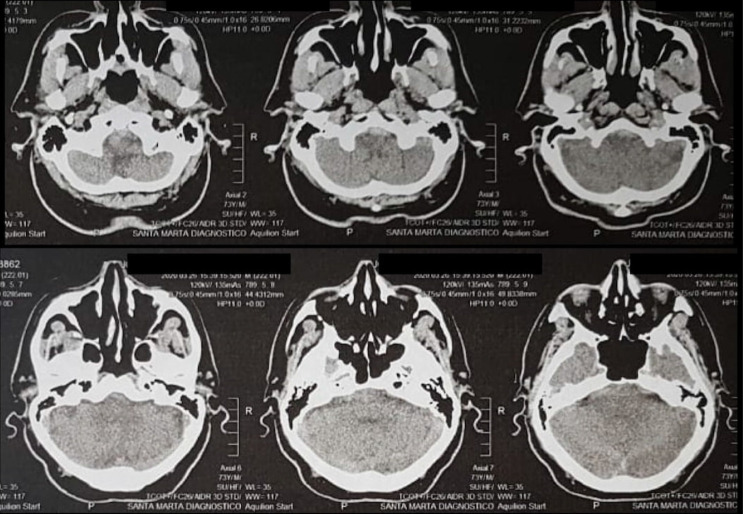

小脑后下动脉(PICA)夹层动脉瘤是一种不常见的病变。其解剖结构和夹层位置各不相同,但通常发生在小脑后下动脉的起源部位。夹层的 PICA 动脉瘤通常无血管形态,涉及整个动脉段,无法切开。尽管如此,近年来这类血管性病变的发现率有所上升,因此有必要对其进行识别,并采取适当的处理方式。在本报告中,我们描述了一例 73 岁的男性患者,他有严重的头痛病史,伴有颈部僵硬、恶心、呕吐、头晕、活动不足、精神错乱和行走困难。通过脑计算机断层扫描(CT)进行的放射学检查显示,髓质前和桥脑前海绵体有轻微出血,脑血管造影显示有一个剥脱性 PICA 动脉瘤。尽管治疗难度很大,但患者还是选择了显微手术治疗。手术在 P2/3 节段之间进行了端对端吻合,临床和影像学效果良好。我们讨论了这个不寻常的病例,回顾了有关临床表现、PICA 夹层动脉瘤血管造影特点的现有文献,并评估了接受显微手术治疗的患者的临床和血管造影结果。

Dissecting posterior inferior cerebellar artery (PICA) aneurysms are uncommon lesions. Their anatomy and the location of the dissection are variable, however, they usually occurs at the origin of the PICA. Dissecting PICA aneurysms generally have non-vascular morphology involving an entire segment of the artery and cannot be cut. Nevertheless, the detection of these vascular lesions has increased latterly, so it is necessary to recognize it and take the appropriate management modalities for these injuries. In this report, we describe a case of a 73-year-old male patient, who presented a history of severe headache, associated with neck stiffness, nausea, vomiting, dizziness, hypoactivity, mental confusion, and walking difficulty. Radiographic investigation with brain computed tomography (CT) showed mild bleeding in a pre-medullary and pre-pontine cistern, and cerebral angiogram showed a dissecting PICA aneurysm. Despite being a challenging treatment, microsurgery management was the chosen modality. It was performed an end-to-end anastomosis between the p2/p3 segments, showing to be effective with good clinical and radiographic outcomes. We discussed an unusual case, reviewing the current literature on clinical presentations, the angiographic characteristics of the dissecting aneurysms of PICA, and evaluating the clinical and angiographic results of patients undergoing microsurgical treatment.